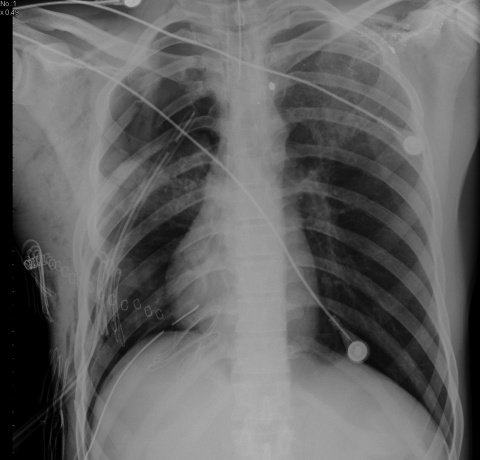

Patienten mit penetrierenden thorakoabdominellen Kombinationsverletzungen stellen eine große

Herausforderung für das behandelnde Team dar (Abb. 1). Sie sind gekennzeichnet durch einen hohen Bedarf an operativen Interventionen und gehen insbesondere als Zwei-Höhlen-Verletzung mit einer hohen Mortalität einher. Speziell Zwerchfellrupturen werden in signifikanter Anzahl, bis zu über 30 %, diagnostisch im Rahmen der CT nicht erkannt. Die mediane Laparotomie als transabdomineller Zugang stellt den Standard bei relevanten perforierenden thorakoabdominellen Verletzungen dar. Verletzungen wie Hohlorganperforationen oder Zwerchfellläsionen lassen keinen konservativen Ansatz zu. Die Laparoskopie bzw. Thorakoskopie ist hierbei gut zum Ausschluss von Hohlorganperforationen und insbesondere auch zum Nachweis nicht detektierter Zwerchfellverletzungen geeignet.